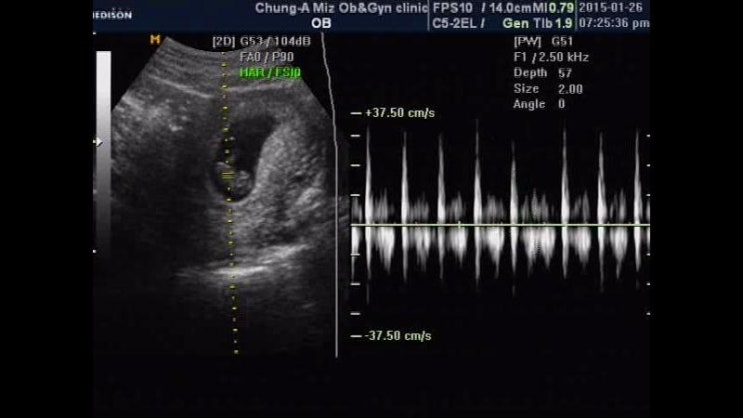

8주4일♡ 젤리곰은 못봣지만

오늘 리언이 만나고왓어요 젤리곰을 기대하고갓는데 배초음파라 선명하진 않앗지만 우렁찬 소리를 듣고오니...